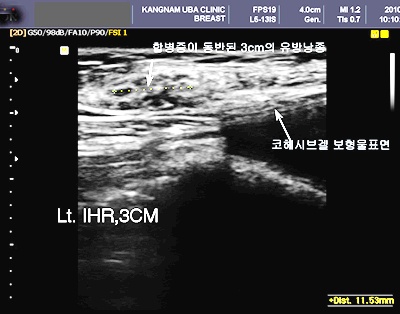

# M¾¾(30/¿©)´Â Æò¼Ò º°·¯¿À´ø °¡½¿ È®´ë ¼ö¼úÀ» ¹Þ±â·Î Çß´Ù. J¾¾´Â Å« ¸¶À½À» ¸Ô°í ¼ºÇü¿Ü°ú Àü¹®ÀÇÀÇ »ó´ãÀ» ¹Þ°í °Üµå¶ûÀÌ Àý°³¸¦ ÇÑ ÈÄ ´ëÈä±Ù ¾Æ·¡ ÄÚÇì½Ãºê°Ö º¸Çü¹°À» ³Ö´Â ½Ã¼úÀ» ¹Þ¾Ò´Ù. ¼ö¼ú °á°ú´Â ¸¸Á·½º·¯¿ü°í ¼ö¼ú ÈÄ ÇÑ ´Þ Á¤µµ Áö³ªÀÚ º×±â°¡ ºüÁö°í °¡½¿ÀÌ ¾î´À Á¤µµ ÀÚ¸®¸¦ ÀâÀÚ º¼·ý°¨°ú ¸ð¾çÀÌ ¸¶À½¿¡ ½ï µé¾ú´Ù.

±×·±µ¥ ÇѰ¡Áö ¹®Á¦°¡ ÀÖ¾ú´Ù. °¡½¿À» ¸¸Áö´Âµ¥ Æò¼Ò¿¡ ´À³¢Áö ¸øÇß´ø ȤÀÌ ¸¸Á®Á³´ø °Í. ¡®¼ö¼ú ÈÄ ºÎ±â ¶§¹®À̰ÚÁö¡¯¶ó°í »ý°¢ÇÏ±â ¸î ´ÞÀ» ±â´Ù·ÈÁö¸¸ ȤÀº ¾ø¾îÁöÁö ¾Ê¾Ò°í ÇÒ ¼ö¾øÀÌ ¼ö¼úÀ» ÇÑ ¼ºÇü¿Ü°ú¸¦ ã¾ÒÁö¸¸ ÀÇ»ç´Â À¯¹æ¿Ü°ú¸¦ ÃßõÇß´Ù.

°á·ÐºÎÅÍ ¸»ÇÏÀÚ¸é J¾¾´Â À¯¹æ¾Ï ÆÇÁ¤À» ¹Þ¾Ò´Ù. Æò¼Ò ±×·¸°Ô ¹Ù¶ó´ø °¡½¿ È®´ë ¼ö¼úÀ» ¹Þ¾ÒÁö¸¸ À¯¹æ¾ÏÀ¸·Î ÀÎÇØ °¡½¿ º¸Çü¹°Àº ¸ðµÎ Á¦°ÅÇØ¾ß¸¸ Çß°í ÇÑÂÊ °¡½¿µµ ¸ðµÎ ÀýÁ¦ÇÑ Ã¤ Ç×¾ÏÄ¡·á¸¦ ¹Þ°í ÀÖ´Ù.

°¡½¿ È®´ë ¼ö¼ú Àü ÇʼöÄÚ½º À¯¹æ¾Ï °Ë»ç¸¦ »©¸ÔÀº ¶§¹®ÀÌ´Ù. À¯¹æ¾Ï Àü¹®ÀǵéÀº °¡½¿ È®´ë ¼ö¼úÀ» ¹Þ±â Àü¿¡´Â ¹Ýµå½Ã À¯¹æ¾Ï °Ë»ç¸¦ ¹Þ¾Æ¾ß ÇÑ´Ù°í ¸»Çϰí ÀÖ´Ù. ÀÌ¹Ì ¹ß»ýÇÑ À¯¹æ¾ÏÀ̳ª À¯¹æÀÇ ¾ç¼º Á¾¾çÀ» °£°úÇÑ Ã¤ °¡½¿ È®´ë ¼ö¼úÀ» ¹ÞÀ¸¸é º¸Çü¹°·Î ¸»¹Ì¾Ï¾Æ À¯¹æ Á¶Á÷ÀÇ º¯È­°¡ ¿À°Ô µÇ°í ÀÌ´Â À¯¹æ¾ÏÀÇ Á¶±â ¹ß°ß¿¡ Ä¡¸íÀûÀÎ °á°ú¸¦ ³»°Ô ÇÒ ¼öµµ ÀÖ´Ù.

¡°ºñ´Ü À¯¹æ¾ÏÀÌ ¾Æ´Ï´õ¶óµµ ¿©¼º¿¡¼­´Â À¯¹æ³¶Á¾À̳ª ¼¶À¯¼±Á¾ µî ¾ç¼º Á¾¾çµéÀÌ ¸¹Àº ¿©¼ºµé¿¡°Ô¼­ ¹ß°ßµÇ´Âµ¥ ƯÈ÷ À¯¹æÈ®´ë¸¦ ÇÒ °æ¿ì º¸Çü¹°¿¡ ÀÇÇÏ¿© Ç¥¸éÀ¸·Î ¿Ã¶ó¿À¸é¼­ ÀÌÀü¿¡´Â Àß ¸¸Á®ÁöÁö ¾Ê´ø ȤµéÀÌ ¸¹ÀÌ ¸¸Á®Áø´Ù¸ç ºÒ¾ÈÇØ ÇÏ´Â ¿©¼ºµéÀÌ ¸¹ÀÌ ÀÖ´Ù.